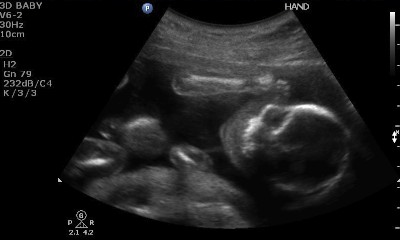

We had our 20 week ultrasound today! Here are some of my favorite pictures that were captured:

Face and right arm/hand (head is on the right)